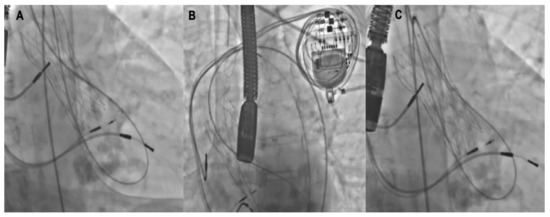

Technical Recommendations for Real-Time Echocardiography and Fluoroscopy Imaging Fusion in Catheter-Based Mitral Valve Paravalvular Leak and Other Procedures

Widespread catheter-based interventions for structural heart disease have overtaken the treatment of paravalvular leaks (PVL). Multimodality imaging techniques play a crucial role in accurate diagnosis, procedure planning and performance. However, PVL closure is often technically challenging due to the complex anatomy of the [...] Read more.

Widespread catheter-based interventions for structural heart disease have overtaken the treatment of paravalvular leaks (PVL). Multimodality imaging techniques play a crucial role in accurate diagnosis, procedure planning and performance. However, PVL closure is often technically challenging due to the complex anatomy of the defects and their relation to surrounding anatomical structures. The application of echocardiography and fluoroscopy imaging fusion (EFF) may simplify challenging imaginative three-dimensional reconstruction of the intracardiac anatomy and facilitate the procedure. To master new technology, personnel must make cognitive changes, overcome a learning curve, and obtain adequate theoretical knowledge. Main aim of this manuscript is to present basic recommendations for EFF application in practice, alongside, each scenario is supported by technically challenging clinical examples. We may conclude that our manuscript may provide useful information for physicians on EEF application in clinical practice. Full article

Show Figures

Figure 1